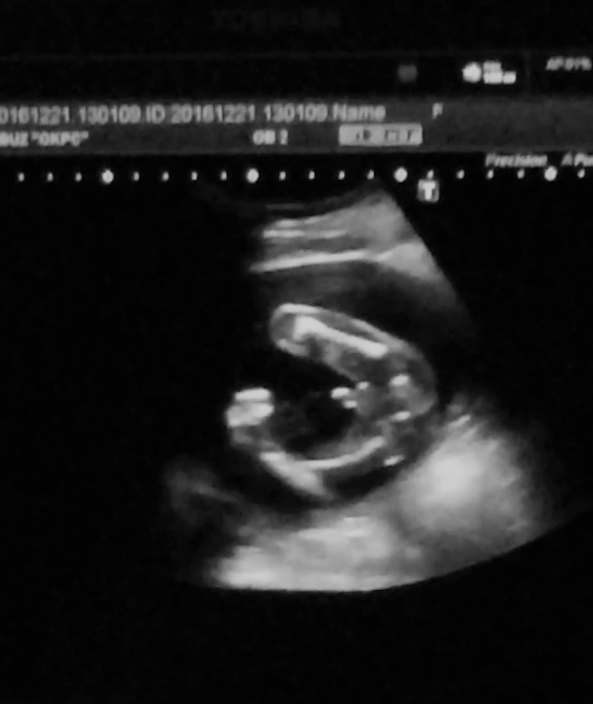

Сегодня 20 недель начались с похода на скрининг))) Нам там подтвердили сынульку, все с нами ттт хорошо, отклонений не выявлено по узи ставят 20+5 неделек) БПР -49мм , написали один живой плод в головном предлежании, плацента расположена по передней и задней стенкам левому ребру, лежим мы поперек маминого животика и я это прекрасно чувствую, буянит сын) головка справа,попка слева ))) Кол-во вод в норме шейка матки 39 мм)

В общем все хорошо и я счастлива) По состоянию все гуд, иногда только тянет связки по бокам, и то что он вытягивается когда лежит поперек доставляет дискомфорт конечно, но не такой уж и сильный) А так все замечательно)) ну и вот наш профиль и засняли нам наше достоинство)) и фотопузик)))